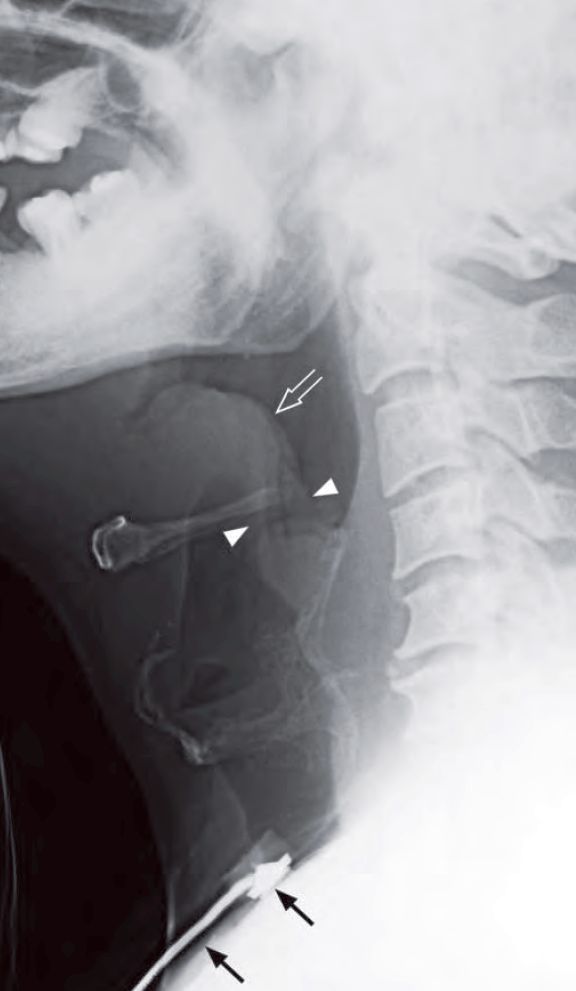

Lateral radiograph of the neck shows a markedly thickened epiglottis (open arrow) – ‘thumb sign’. Also note the thickened aryepiglottic folds (arrowheads) due to tracking of the infection from epiglottis. Features are highly suggestive of acute epiglottitis. Note the tube in the trachea to maintain the air way (arrows).

- Markedly swollen epiglottis with ‘thumb-printing’ appearance

- Thickening of aryepiglottic folds